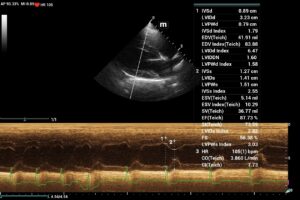

14Kg KCCS Dog; 3/6 murmur placed on Pimo after rads. Echo(3 wks later) revealed mild mod MV reg, TV reg and AO ins. PG – MV and TV=N. AO PG=N with plateau flow profile. Echo = stage B1 MVD, BP= N.Dog was 5 lbs ovweight. C index adj. to 11.7Kg= N.

Q: Could Pimo use be + affecting the LV size?

Sonographically B1 and B2 I go to the atrial septum and ensure its deviated toward the right atrium and not in line wiht the IVS. Your echo the AS is in line wiht the UVS and not deviated and there fore no LAE in this case. I use the LA max measurement and ensure there is a solid MR jet and not a small one. I dont have rads available in many of my interps so from the sonographer perspective this tends to work well. If pimo other tx has been given and the LA is normal and you dont know if the LA is normal because of tx or its normal because it didnt need it, then I go to the level of MR because the MR has to have. alarge regurguitant flow to eventually cause LA enlargement. Then of course checking rads to see if they misinterpreted the rads as LAE which happens a lot. Otherwise stop the pimo for a week and rescan and see what the lA is doing. If just B2 they should be good wihtout tx for a week to find out if the tx direction is correct. Your case looks very B1. Hope this helps

No LAE on rad, VLAS =1.74,VHS = high normal for a KCCS 11.78. Echo was normal. The heart had a few minor “leaks” , dog was being treated and the owner felt the dogs activity and energy improved on meds. Wasn’t sure if increased quality noted in a B1 dog put on meds would warrant continuation or one should always follow protocol. It’s possible owner subjectivity could be biased too.Will stop meds and observe response.